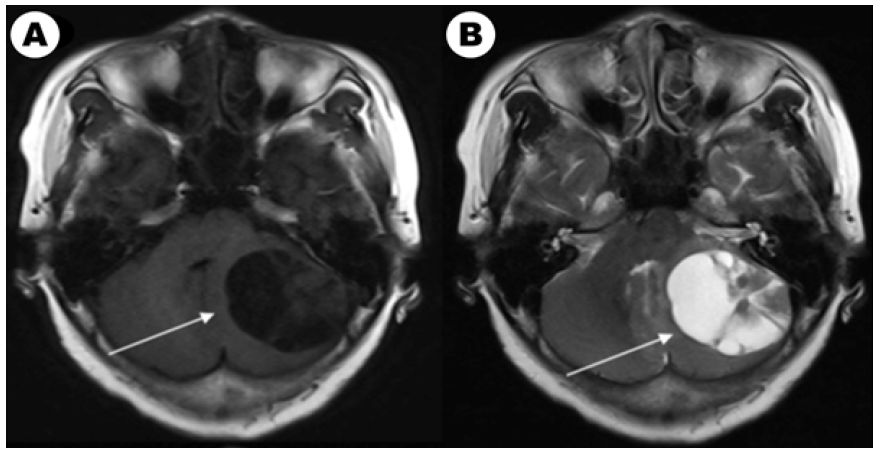

Figure 1A: The brain enhanced MRI of a 61-year-old woman with non-small lung cancer and EGFR 21L858R mutation before and after EGFRTKI treatment. Contrast-enhanced T1-weighted MR image in baseline. Figure 1B: Contrast-enhanced T2-weighted MR image in baseline.

Figure 1C: Contrast-enhanced T1-weighted MR image after EGFR-TKI target therapy and whole brain radiotherapy (the prescription dose and fraction schedule were 30Gy/10F) treatment one month. Figure 1c: Contrast-enhanced T2-weighted MR image after EGFR-TKI target therapy and whole brain radiotherapy treatment one month.

According to our follow-up, 4 patients abandoning therapy and 33 patients which received treatment had evaluable efficacy. Until the last follow-up time, 40 patients had evaluated overall survival and 8 (8/40, 20.0%) patients were still alive. Among them, 14 patients with EGFR/ALK gene mutated had TKI targeted treatment and 19 patients received chemotherapy. For brain radiotherapy, 4 of 14 EGFR/ALK mutated patients received radiotherapy and 12 of 19 patients received chemotherapy had brain radiotherapy. We also compared characteristics between patients received targeted drugs and chemotherapy in (Table 2). We showed a typical case of cystic BM which was EGFR mutated NSCLC patient in (Figure 1A). We showed the baseline brain MRI images in(Figure 1A) (T1-weighted MR image) and(Figure 1C) (T2-weighted MR image). After one month of icotinib-targeted therapy and whole brain radiotherapy, the brain MRI images of the patient presented in (Figure 1C) (T1-weighted MR image) and (Figure 1C) (T2-weighted MR image). The effect+- -+-+-+++-` of this patient showed that the brain lesion had shrunk significantly.